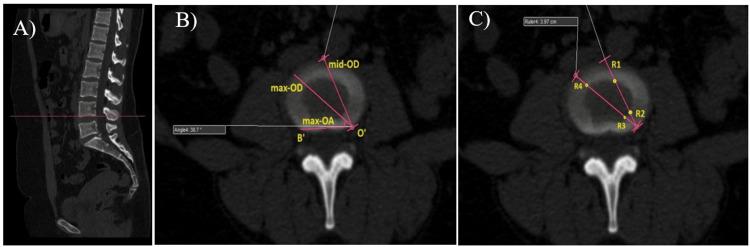

Background Lumbar fusion techniques are vital for treating various spinal conditions by promoting vertebral fusion to alleviate pain and restore stability. Given the anatomical uniqueness of the Indian skeletal structure, this study evaluates the radiological dimensions of lumbar endplates in the Indian population and their correlation with the placement and length of interbody cages used in various lumbar fusion techniques such as oblique lateral lumbar interbody fusion (OLIF), transforaminal lumbar interbody fusion (TLIF), and anterior lumbar interbody fusion (ALIF). This study aimed to conduct radiological measurements of lumbar endplates in the Indian population and correlate them with cage placement and length in lumbar fusion techniques. Methods This prospective study was conducted at the orthopaedic ward of a tertiary care center in Western Maharashtra, India. Healthy individuals (aged >18 years, either gender) selected with a 95% confidence level using Philip Core Integrity software (Amsterdam, Netherlands) were included in the study. We excluded those with a history of low back pain, previous lumbar spine surgeries, fractures, tuberculosis, tumors, deformities, degenerative diseases, or lesions affecting the lumbar spine. Quantitative measurements such as oblique and sagittal diameters, apophyseal ring widths, and interbody cage lengths were calculated using multiplanar reformatting with specific imaging parameters. Results A total of 150 individuals with an average age of 39.83 ± 14.17 years, ranging from 20 to 65 years. Among the study population, 68 were males and 82 were females. Among the male study population, oblique parameters such as Angle AOB and Mid-OD (oblique diameter) show considerable variability, with Angle AOB ranging from 51.43 ± 2.40 mm (L2 inferior) to 31.59 ± 4.25 mm (L5 inferior) and Mid-OD ranging from 41.59 ± 2.59 mm (L3 superior) to 34.38 ± 2.26 mm (S1 superior). Side-sagittal dimensions vary from 32.11 ± 2.50 mm (S1 superior) to 36.48 ±3.26 mm (L3 superior), emphasizing the need for tailored surgical planning. In contrast, females in the study population exhibit distinct anatomical profiles, with Angle AOB ranging from 52.15 ± 2.43 mm (L2 inferior) to 20.45 ± 5.45 mm (S1 superior) and Mid-OD from 33.48 ± 2.15 mm (L3 inferior) to 42.45 ± 2.59 mm (L3 superior). These findings underscore gender-specific anatomical differences crucial for individualized clinical evaluation and treatment strategies. Conclusion This study comprehensively analyzes oblique, side-sagittal, transverse, and midsagittal anatomic parameters across various vertebral levels in men and women, highlighting significant anatomical variations crucial for clinical assessments and surgical interventions.

背景 腰椎融合技术通过促进椎体融合以减轻疼痛并恢复稳定性,对治疗各种脊柱疾病至关重要。鉴于印度骨骼结构的解剖学独特性,本研究评估了印度人群腰椎终板的放射学尺寸,以及它们与各种腰椎融合技术(如斜外侧腰椎椎间融合术(OLIF)、经椎间孔腰椎椎间融合术(TLIF)和前路腰椎椎间融合术(ALIF))中使用的椎间融合器的放置和长度的相关性。本研究旨在对印度人群的腰椎终板进行放射学测量,并将其与腰椎融合技术中融合器的放置和长度相关联。方法 本前瞻性研究在印度马哈拉施特拉邦西部一家三级医疗中心的骨科病房进行。使用飞利浦Core Integrity软件(荷兰阿姆斯特丹)以95%的置信水平选取的健康个体(年龄>18岁,不限性别)纳入本研究。我们排除了有腰痛病史、既往腰椎手术史、骨折、结核、肿瘤、畸形、退行性疾病或影响腰椎的病变的个体。使用具有特定成像参数的多平面重组计算诸如斜径和矢状径、骨突环宽度和椎间融合器长度等定量测量值。结果 共有150名个体,平均年龄为39.83±14.17岁,年龄范围为20至65岁。在研究人群中,男性68名,女性82名。在男性研究人群中,诸如AOB角和中间外径(斜径)等斜向参数显示出相当大的变异性,AOB角范围从51.43±2.40毫米(L2下终板)到31.59±4.25毫米(L5下终板),中间外径范围从41.59±2.59毫米(L3上终板)到34.38±2.26毫米(S1上终板)。侧矢状径尺寸从32.11±2.50毫米(S1上终板)到36.48±3.26毫米(L3上终板)不等,强调了定制手术规划的必要性。相比之下,研究人群中的女性表现出不同的解剖学特征,AOB角范围从52.15±2.43毫米(L2下终板)到20.45±5.45毫米(S1上终板),中间外径从33.48±2.15毫米(L3下终板)到42.45±2.59毫米(L3上终板)。这些发现强调了性别特异性解剖学差异对个体化临床评估和治疗策略至关重要。结论 本研究全面分析了男性和女性不同椎体水平的斜向、侧矢状、横向和矢状中解剖参数,突出了对临床评估和手术干预至关重要的显著解剖学变异。